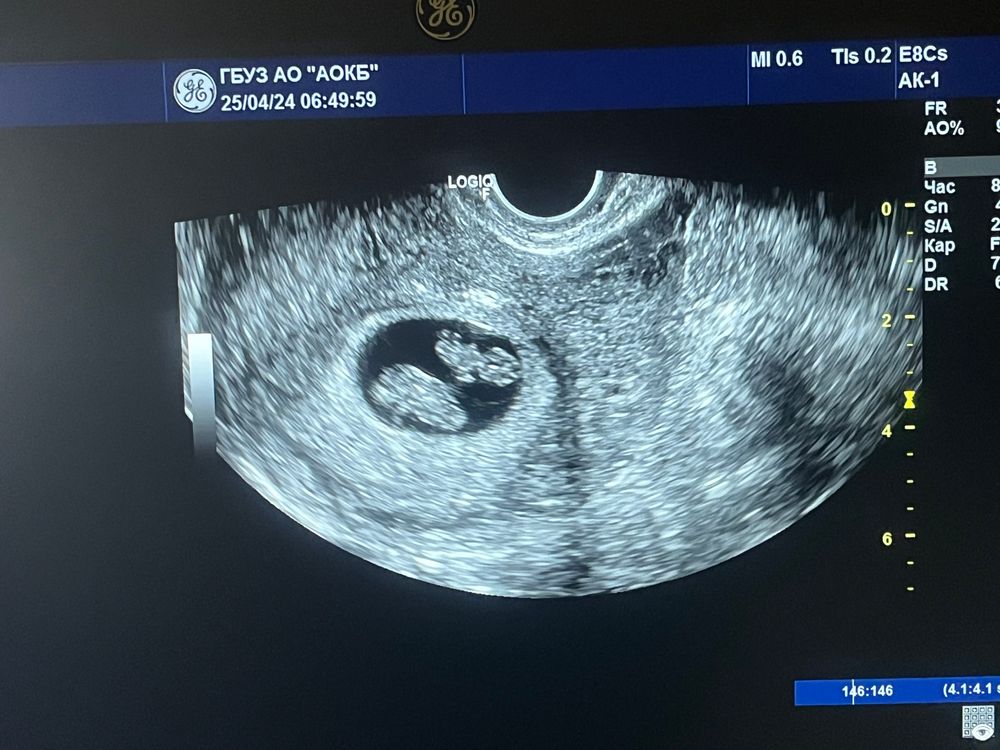

Екатерина, 8 недель

Марта Кошкина, правда не 6-7 а 8.1

Как две фасолинки)))